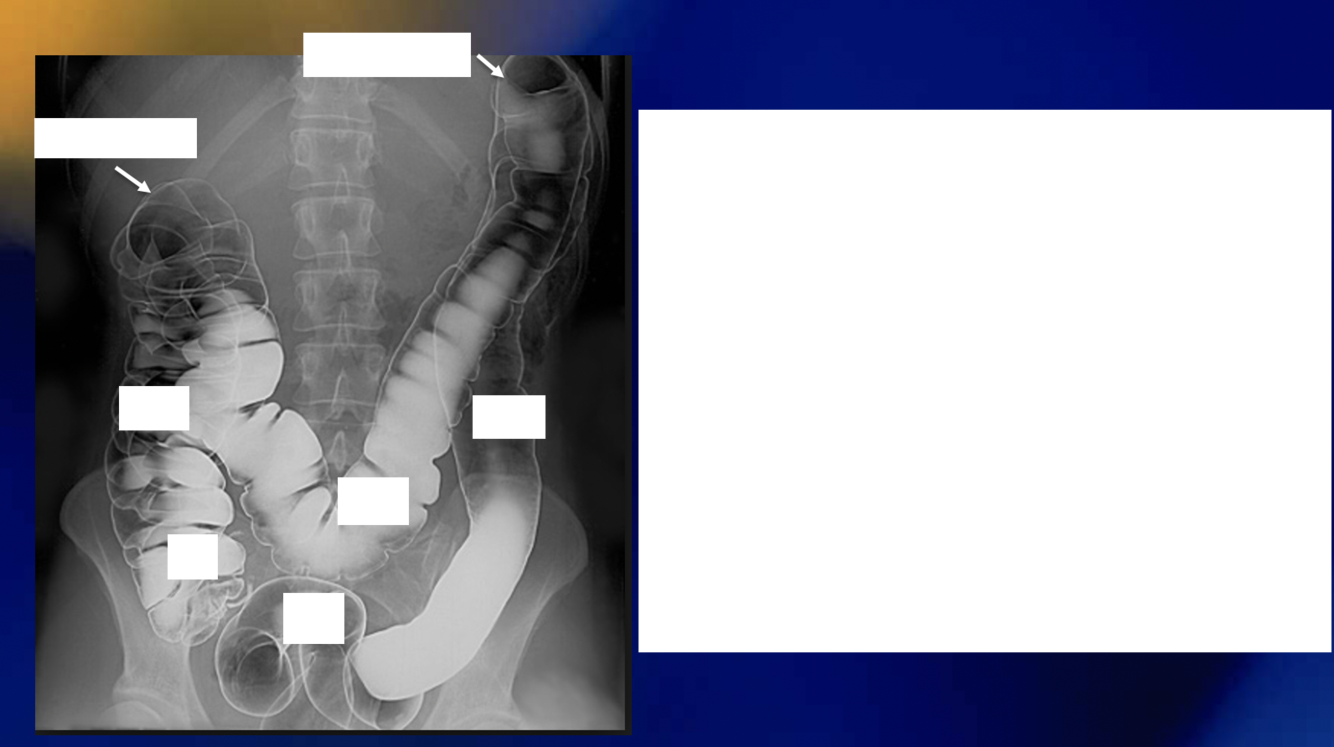

How can you differentiate between the small and large intestines in xray?